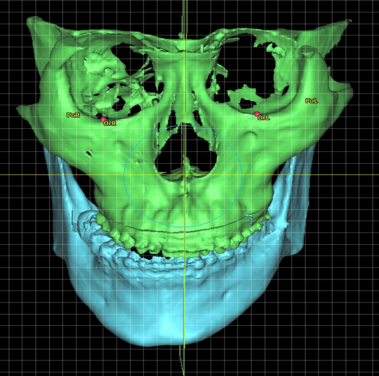

Facial asymmetry can be a result of the difference in jaws’ growth rate or caused by trauma. Patients with facial asymmetry will see a difference in the length of the left and right side of the jaws, which result in a deviated face as well as a shifted bite. The asymmetric face not only affects the facial appearance of the individual, but also hinders the eating or speech function and lowers the patient’s self-esteem.

In the study, Dr Leung’s team investigated the prevalence of TMDs in 134 patients. Among them, 82 were with facial asymmetry while 52 with other facial deformities without asymmetry.

It was found that the prevalence of TMD in patients with facial asymmetry was 67.1%, which was significantly higher than those without (40.4%). Of these patients with facial asymmetry, 78.2% are presented with temporomandibular joint (the joint which connects the lower jaw to the skull) (TMJ) disc displacement with reduction, 34.5% have myalgia (muscle pain), and 20% have arthralgia (joint pain) (Note 1). The study shows that patients with dentofacial deformity, in particular facial asymmetry, are much more likely to suffer from TMD than individuals without such deformity.